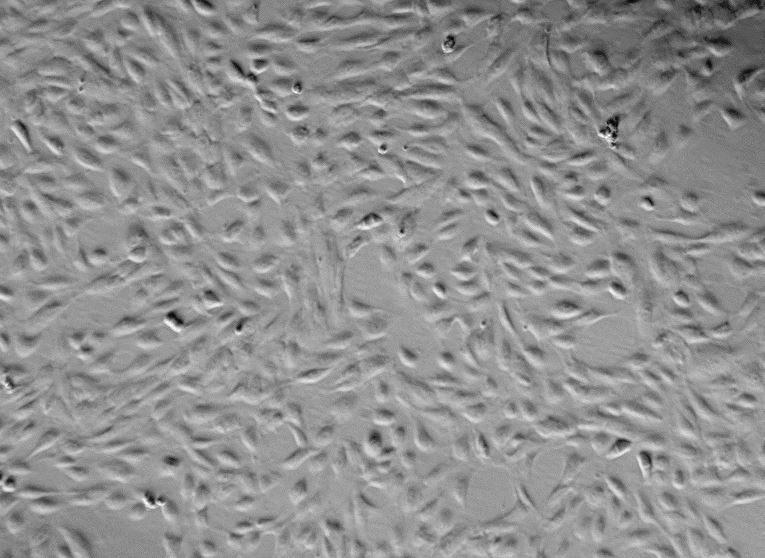

Human Primary Pulmonary Artery Endothelial Cells View larger

Human Primary Pulmonary Artery Endothelial Cells

5) Cell growth mode: epithelioid, polygonal cells, adherent culture.